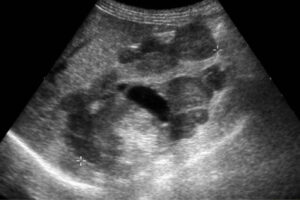

En México, el cáncer renal es una de las enfermedades oncológicas de mayor preocupación para la salud pública. De acuerdo con el Observatorio Mundial del Cáncer (GLOBOCAN), este padecimiento ocupa el lugar número 11 en frecuencia en el país, además 53% de quienes lo padecen fallecen a consecuencia de esta enfermedad.

Por ello, Mayra Galindo, directora general de la AMLCC, consideró de suma importancia colocar la mirada en los pacientes que se enfrentan al cáncer y, particularmente, a quienes viven con cáncer de riñón ya que el 60% de los casos se diagnostican en etapas localmente avanzadas y sólo 2 de cada 10 pacientes tienen una detección temprana.

Proyecciones de la Organización Mundial de la Salud indican que para el año 2040, la incidencia podría aumentar entre un 50% y un 70%, y la mortalidad alcanzar un incremento de hasta el 60%. Por eso, el principal reto es reducir el diagnóstico tardío y atenderlo de forma temprana y efectiva.